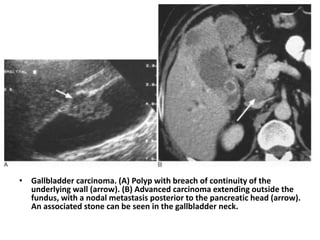

• Gallbladder carcinoma. (A) Polyp with breach of continuity of the

underlying wall (arrow). (B) Advanced carcinoma extending outside the

fundus, with a nodal metastasis posterior to the pancreatic head (arrow).

An associated stone can be seen in the gallbladder neck.

• GALLBLADDER CARCINOMA • Uncommon malignancy that has a very poor prognosis. • presents at a late stage in the sixth and seventh decades with right upper-quadrant pain, often presenting as hilar biliary obstruction. • On imaging as focal or diffuse irregular thickening of the gallbladder wall or as a larger mass in the gallbladder fossa with little or no gallbladder lumen identifiable. Gallbladder stones may appear to be ‘buried’ in the mass. • Spread to lymph nodes around the portal vein relatively early in its course and at presentation there may be nodal masses extending down to the head of the pancreas. • spreads to the adjacent liver (segments 4 and 5). • D/D includes Mirizzi syndrome and metastases to the gallbladder, which are uncommon but include melanoma

• Gallbladder carcinoma.(A) Polyp with breach of continuity of the underlying wall (arrow). (B) Advanced carcinoma extending outside the fundus, with a nodal metastasis posterior to the pancreatic head (arrow). An associated stone can be seen in the gallbladder neck.